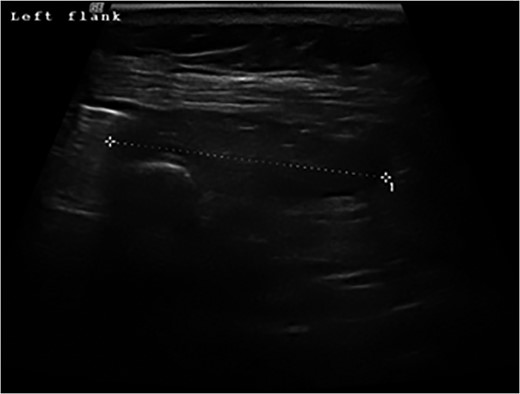

A 72-year-old woman presented with acute lower abdominal pain and nausea. She had not opened her bowels in 5 days and was passing no flatus. Her medical background included Parkinson’s Disease, hypothyroidism, hypertension, pulmonary embolism and deep vein thrombosis. Further history revealed a longstanding swelling in her left flank, diagnosed as a lipoma and excised 15 years ago under local anaesthetic. Interestingly, according to the patient, her swelling was unchanged after the procedure. A community ultrasound done over a year before her acute presentation had suggested the presence of a hernia (Fig. 1); however, the sonographer was not a musculoskeletal specialist and could not confirm the diagnosis. Biopsy only showed subcutaneous fatty tissue and the lump was diagnosed as a recurrent lipoma.

Ultrasound scan of the left flank showing possible hernia in a 72-year-old woman presenting with a flank swelling (dashed line).